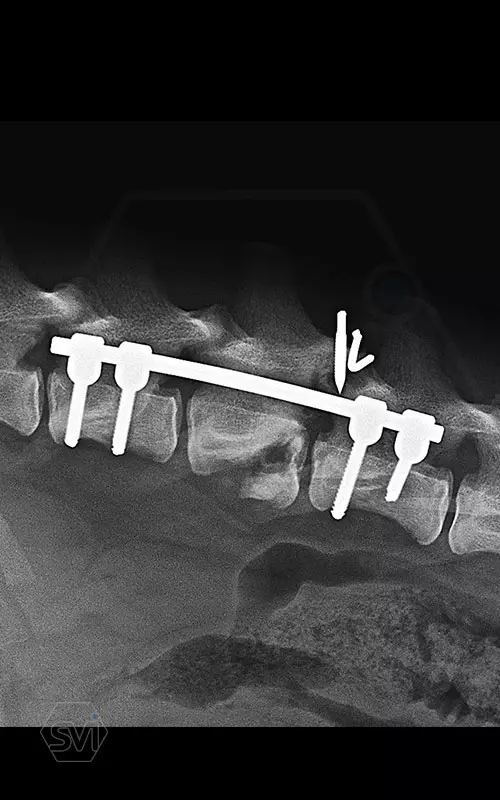

Kutya neve: Benetton, az SOP-LC hatékonysága és stabilitása magáért beszél, a gyógyulás alatt a gerinc folyamatos terhelés alatt volt, és a fémek nem mozdultak el. A kutya szerencsére neurológiailag i felépült! Tehát van esély a gerinctörések esetén is a gyógyulásra...